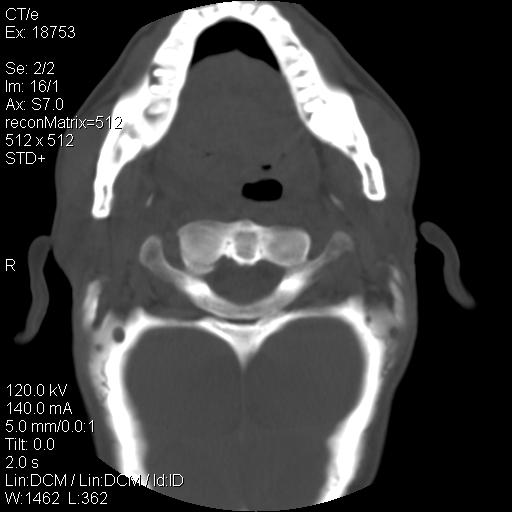

标题: CT21693:男 58岁 右侧咽部疼她2天余 PE:右侧扁桃体肿大 压痛 [打印本页]

标题: CT21693:男 58岁 右侧咽部疼她2天余 PE:右侧扁桃体肿大 压痛

喉部新生物,喉癌可能大,建议喉镜取组织活检。

右化脓性扁桃体炎症伴咽后壁脓肿形成.

结合病史,考虑感染性病变;建议抗炎治疗复查排除肿瘤性病变。